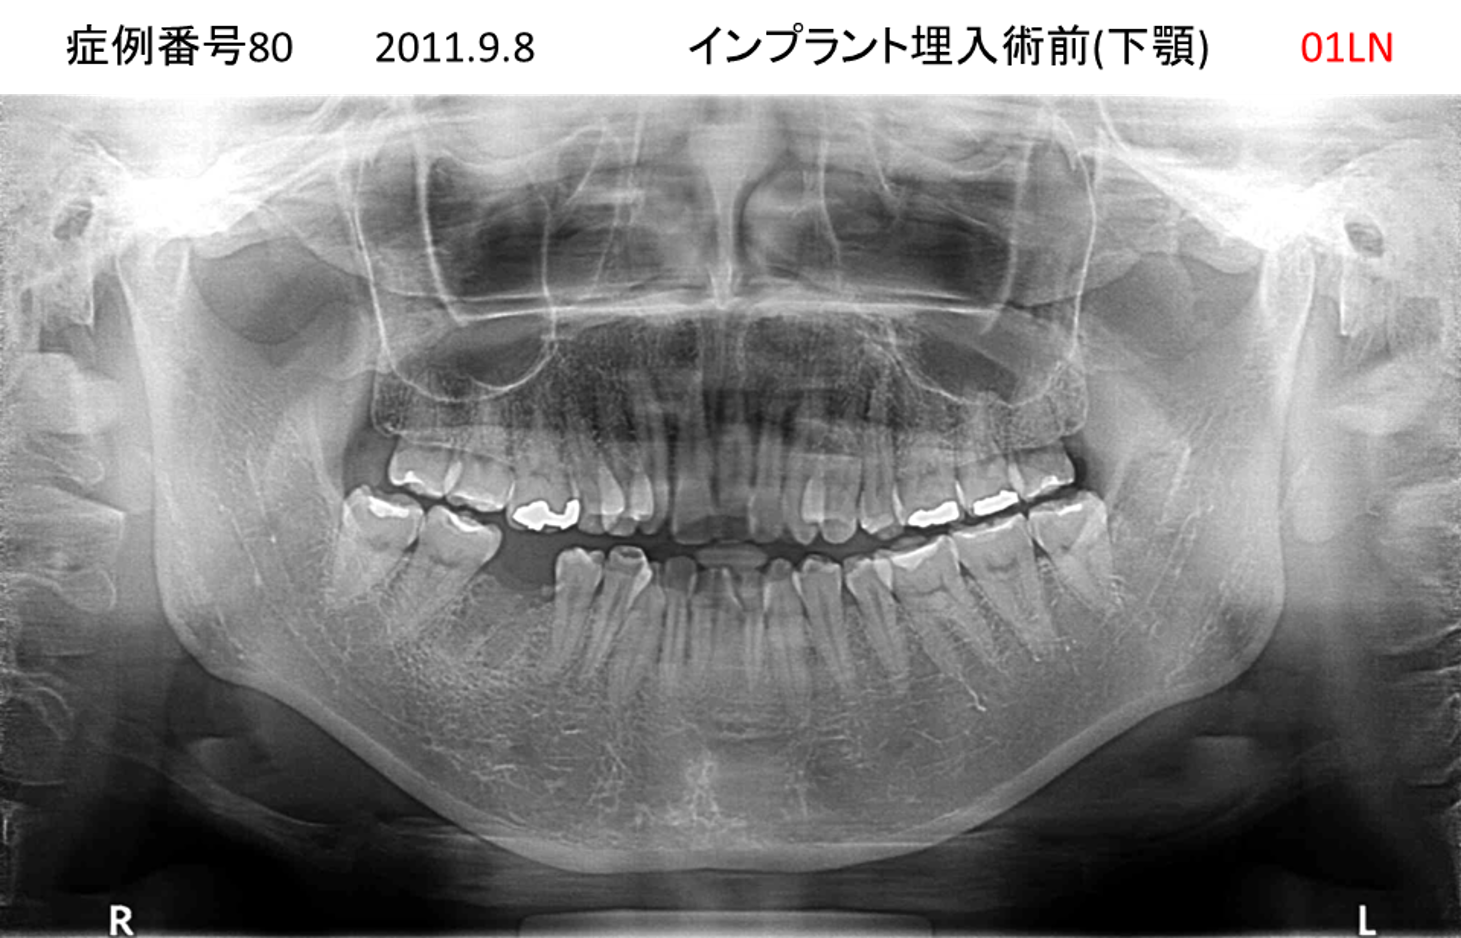

義歯が合わない、噛めない患者様のインプラント症例

| 治療名称 |

インプラントコーヌステレスコープ |

| 治療費用 |

270万円+税 |

| 治療期間 |

4か月 |

| 患者さんの症状(主訴) |

義歯が合わない、噛めない |

| 治療内容 |

インプラント、義歯作製(コーヌステレスコープ) |

| 治療結果 |

しっかり噛めるようになった。見栄えが良くなった。 |

| 治療の注意点(リスク/副作用) |

義歯が壊れた場合、インプラントが壊れた場合は再治療が必要 |